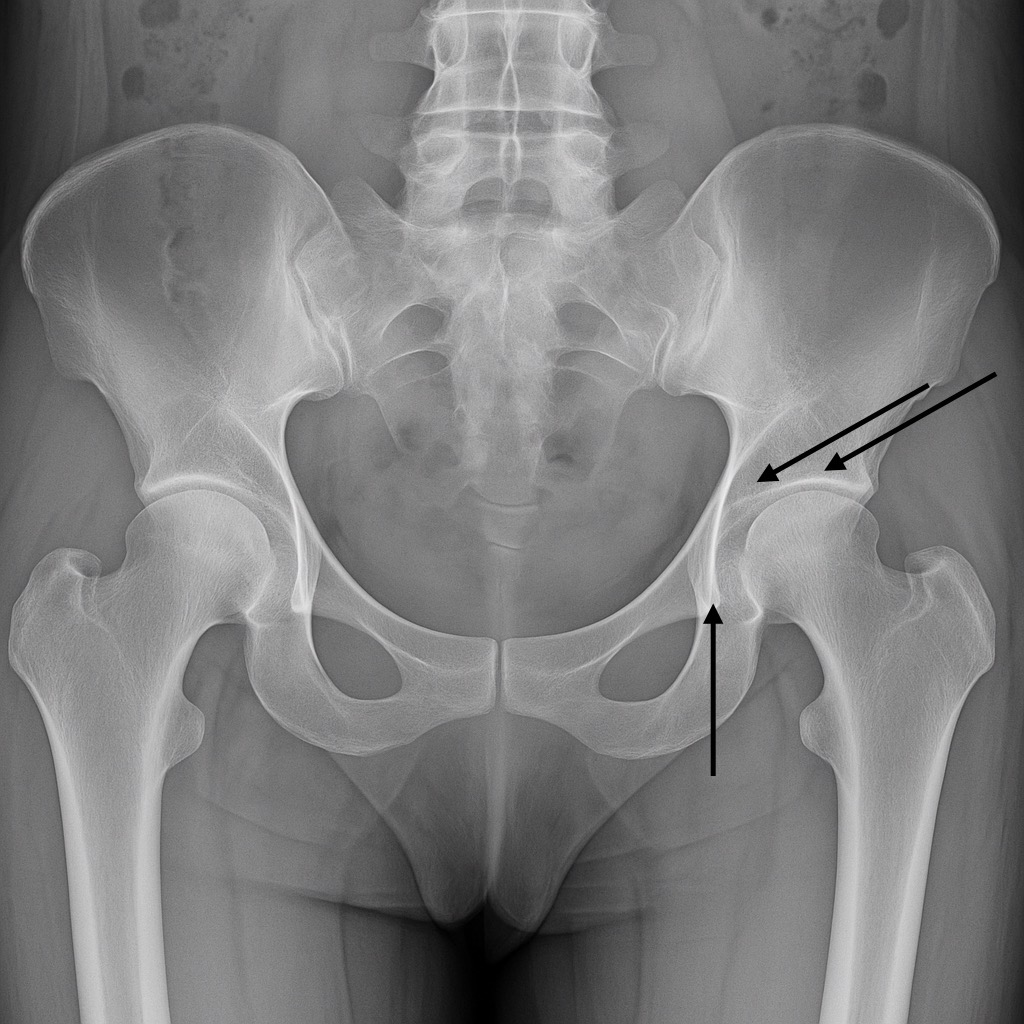

Radiofrecuencia en Articulaciones: Cadera

Indicada para pacientes con artrosis de cadera o dolor persistente luego de reemplazo articular. Se aplican pulsos de radiofrecuencia sobre los nervios sensitivos que rodean la articulación.

Radiofrecuencia de cadera